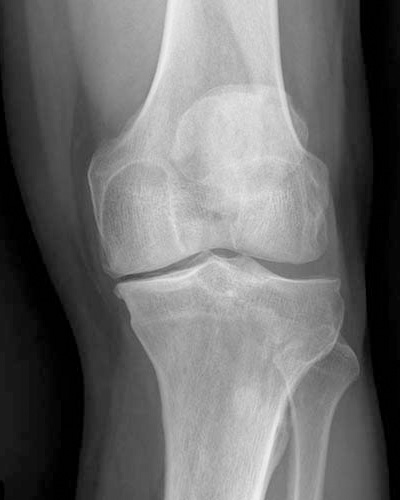

A osteotomia do joelho, geralmente realizada na tíbia ou no fêmur, é um procedimento cirúrgico indicado para pacientes que apresentam artrose localizada em apenas um dos compartimentos do joelho. O termo “osteotomia” refere-se ao corte ósseo realizado com o objetivo de corrigir o eixo do membro inferior, redistribuindo a carga dentro da articulação.

O procedimento consiste na retirada ou adição de uma cunha óssea na tíbia proximal ou no fêmur distal, permitindo que o peso do corpo seja transferido da área comprometida para uma região mais saudável do joelho. A osteotomia é mais frequentemente indicada para pacientes mais jovens, nos quais a substituição total do joelho ainda não é a melhor opção.

A cirurgia consiste na retirada ou inserção de uma cunha óssea na tíbia ou no fêmur, com o objetivo de corrigir o alinhamento da perna. Essa correção reduz a pressão excessiva sobre o compartimento acometido pela artrose, aliviando a dor e melhorando a função do joelho.